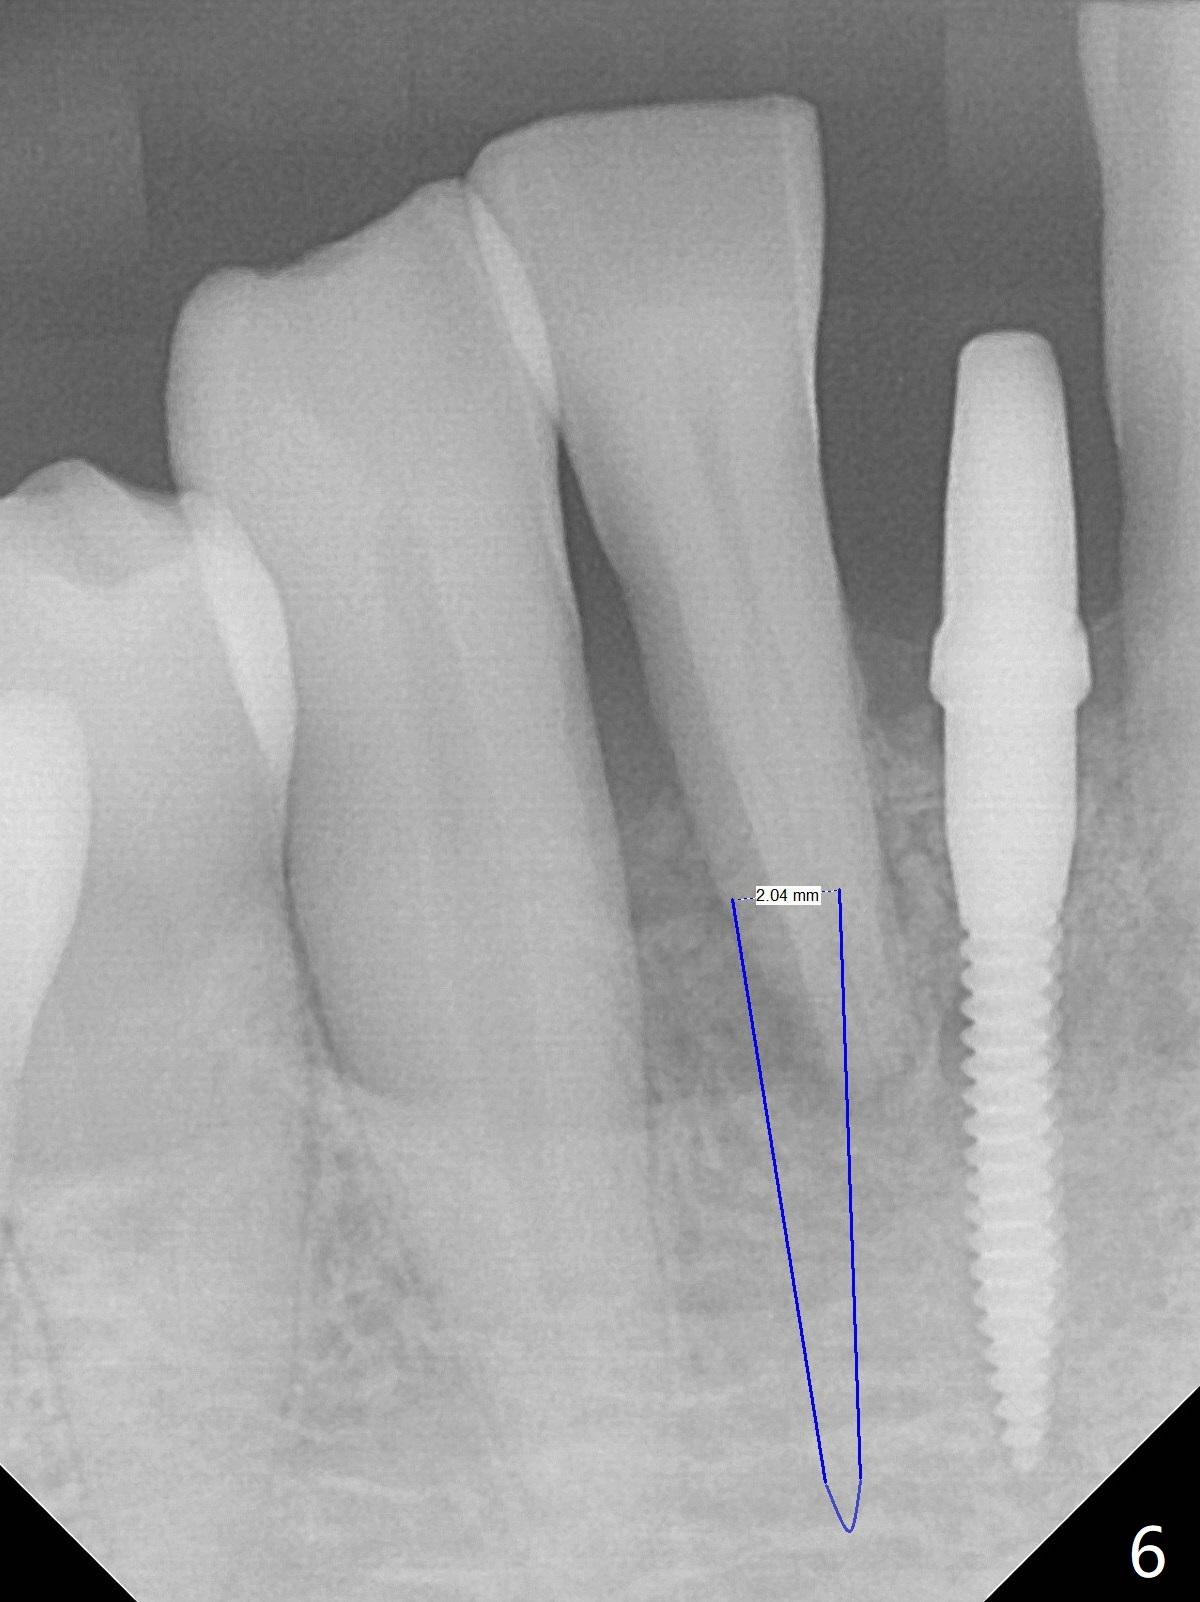

Out of financial concern, the patient does not agree to have the tooth #26 extracted. Due to atrophy of the most coronal ridge buccally at #25 (Fig.1,2 *), osteotomy is initiated difficult and distal (Fig.3). After 1.2 mm drill removal (Fig.3' black area), Lindamann bur is used to move the osteotomy mesial (red area). A 2x12(4) mm 1-piece implant is placed (Fig.4,5); the buccal defect is packed with allograft (Vanilla, .5-1 mm cancellous/cortical mixture, *). When the tooth #26 fails, a 2 mm implant will be placed (Fig.6 blue). Following abutment adjustment, a provisional is fabricated (Fig.7 P); note the lower incisal edges of #25 and 26, as compared to those of the neighboring teeth. To reduce occlusal trauma, the incisal edge of the tooth #26 has been decreased (Fig.5 open arrow). The implant threads seem not to be exposed 4 months postop (Fig.8), although the tooth #26 has mobility II.